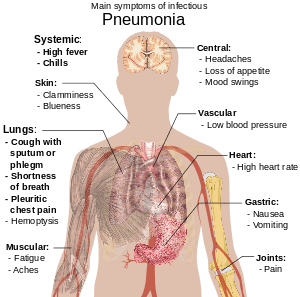

People with infectious pneumonia often have a productive cough, fever accompanied by shaking chills, shortness of breath, sharp or stabbing chest pain during deep breaths, and an increased rate of breathing.[18] In the elderly, confusion may be the most prominent sign.[18]

The typical signs and symptoms in children under five are fever, cough, and fast or difficult breathing.[19] Fever is not very specific, as it occurs in many other common illnesses, may be absent in those with severe disease, malnutrition or in the elderly. In addition, a cough is frequently absent in children less than 2 months old.[19] More severe signs and symptoms in children may include blue-tinged skin, unwillingness to drink, convulsions, ongoing vomiting, extremes of temperature, or a decreased level of consciousness.[19][20]

Bacterial and viral cases of pneumonia usually present with similar symptoms.[21] Some causes are associated with classic, but non-specific, clinical characteristics. Pneumonia caused by Legionella may occur with abdominal pain, diarrhea, or confusion,[22] while pneumonia caused by Streptococcus pneumoniae is associated with rusty colored sputum,[23] and pneumonia caused by Klebsiella may have bloody sputum often described as "currant jelly".[17] Bloody sputum (known as hemoptysis) may also occur with tuberculosis, Gram-negative pneumonia, and lung abscesses as well as more commonly with acute bronchitis.[20] Mycoplasma pneumonia may occur in association with swelling of the lymph nodes in the neck, joint pain, or a middle ear infection.[20] Viral pneumonia presents more commonly with wheezing than does bacterial pneumonia.[21] Pneumonia was historically divided into "typical" and "atypical" based on the belief that the presentation predicted the underlying cause.[24] However, evidence has not supported this distinction, thus it is no longer emphasized.[24]